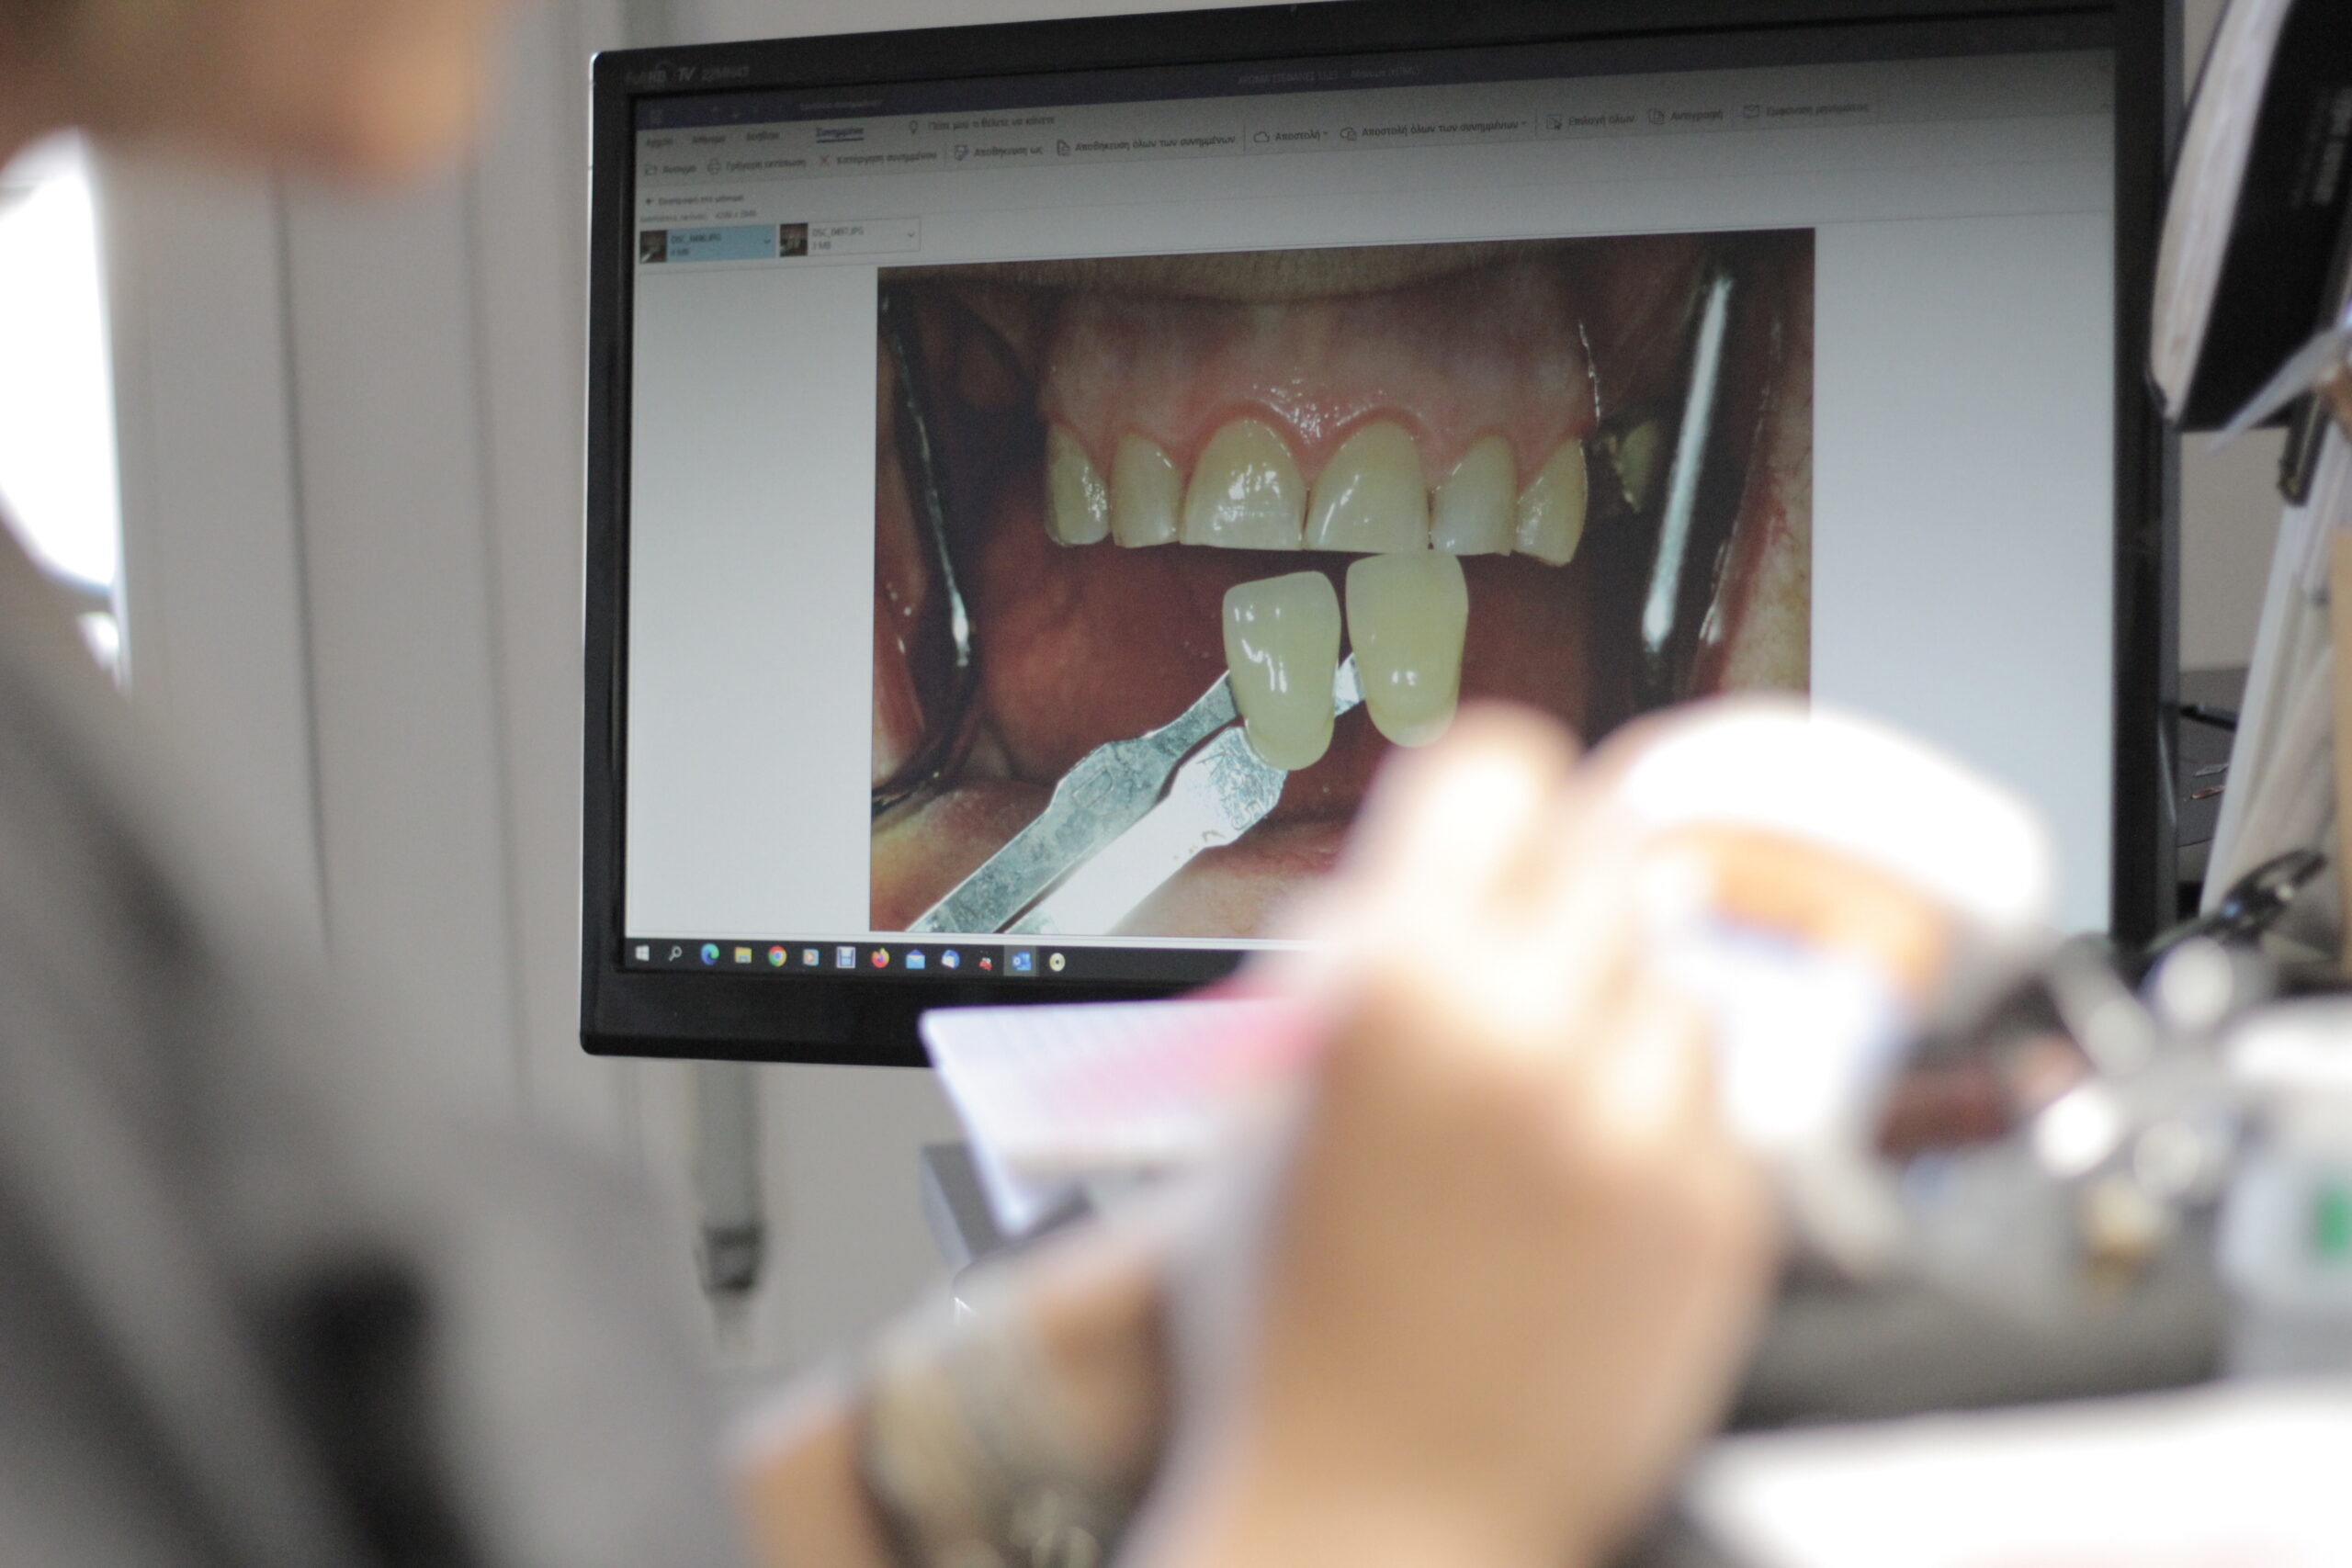

WIR BIETEN EINE VIELZAHL VON ABNEHMBAREN UND FESTEN ZAHNPROTHESEN.

Odontolab ist spezialisiert auf prothetische Restaurationen und bietet Zahnärzten hervorragende,

gut passende, individuelle Restaurationen für ihre Patienten.

Dies kann in zwei große Kategorien unterteilt werden.